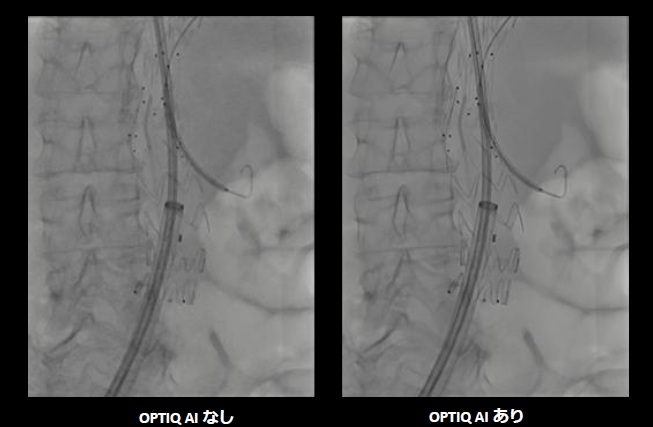

機器に搭載する「OPTIQ AI」は、画像生成プロセスでノイズを大幅に抑制し、高精細で高コントラストな画像出力が可能。CNR(コントラストノイズ比)をベースとした画像処理で、システム条件や患者の体格差、Cアームの角度などに影響を受けない、安定した画像を表示する。

また、AIを活用したアルゴリズムによって、幅広い2D透視・撮影モード、さまざまな部位で、信号強度を維持したまま量子ノイズと電子ノイズのリアルタイム低減を可能にした。装置由来のノイズを抑制することで、微細な血管やカテーテル、ガイドワイヤーなどの治療機器を明瞭に描出し、良好な視認性を確保した。